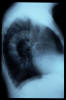

TBC pulmonar antigua